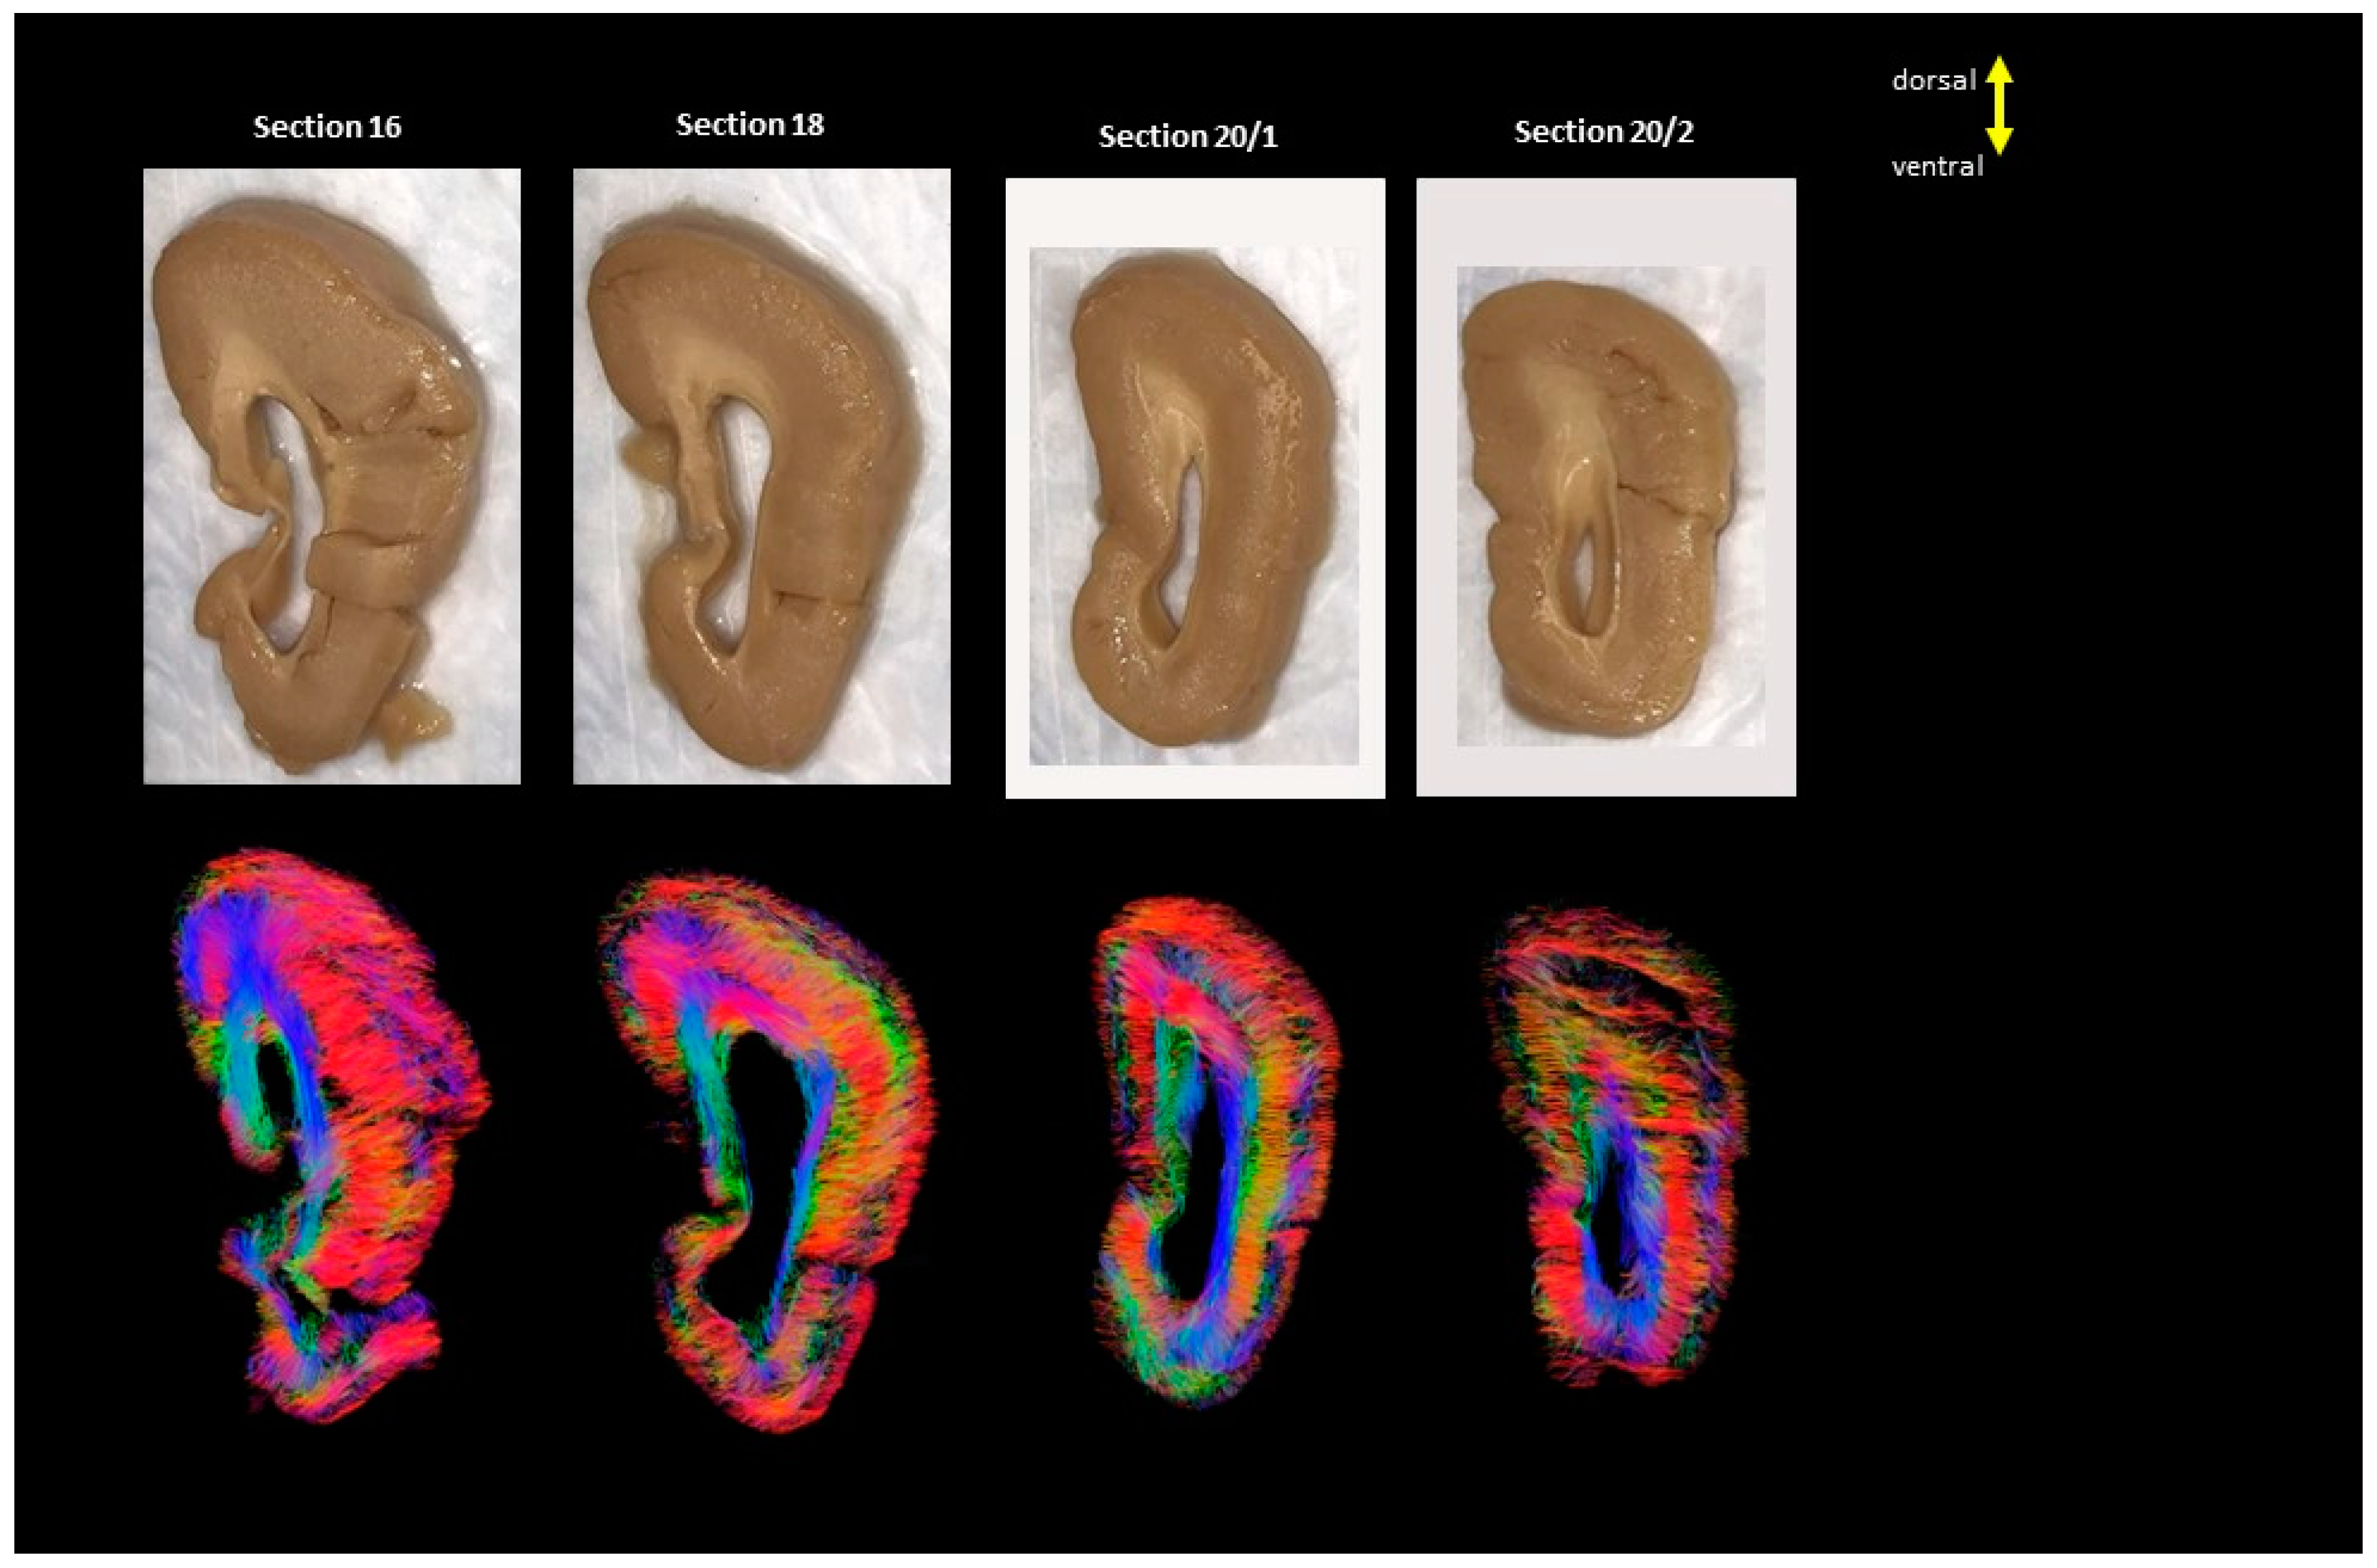

2. Materials and Methods

2.1. Diffusion MRI Acquisition and Analysis

3. Results